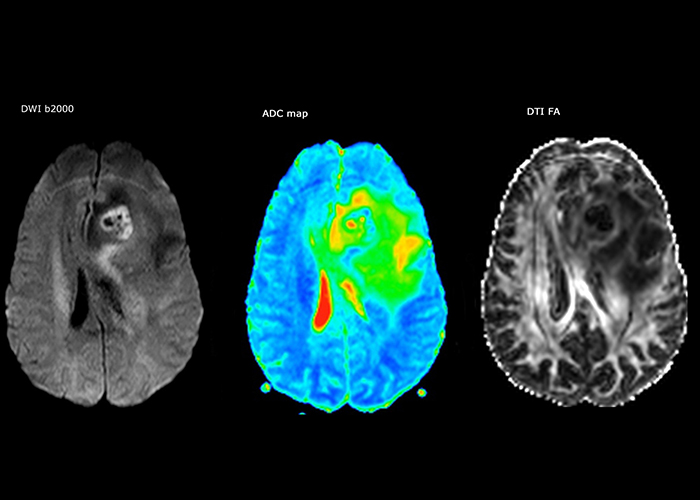

Dr. Savatovsky uses five or six different ExamCards for imaging a mass or a known tumor in the brain. “If there is a mass in the brain we try to characterize it to inform the neurologist for determining next steps or to help neurosurgeon prepare for a surgery or biopsy. For follow-up after treatment we have different protocols for different treatments and we adapt for intra- or extra-axial tumors.”

“The biggest challenges are properly characterizing the lesion and giving the surgeon all the information needed, such as the location of vessels and functional areas. Sometimes a very comprehensive exam is necessary, such as when a mass has been discovered at another hospital after which the patient is referred to us. We then do both lesion characterization and preoperative imaging in one exam, so both morphologic and functional assessment. For morphologic assessment we will use pre- and post-contrast T1-weighted imaging, FLAIR to assess infiltration, and diffusion. For functional characterization we will perform perfusion, spectroscopy, and susceptibility weighted imaging to look for micro vessels or micro hemorrhage inside the lesion[4]. For preoperative imaging we perform specific morphologic imaging that is compatible with the navigation system; depending on the location of the tumor, we would do fMRI or DTI.”

“That is the most comprehensive exam we would do. Ingenia has the good spatial resolution and high SNR to provide all this information, and the flexibility to use shorter sequences, so we can do a very comprehensive examination in a limited time.”